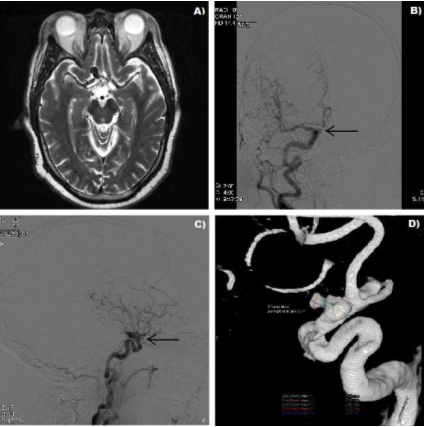

The patient was a 64-year-old male with history of hypertension, chronic obstructive pulmonary disease (COPD) and polycystic kidney disease (PKD) who presented with an episode of headache and dizziness. On physical examination the patient was fully alert and oriented, as well as able to provide his own history. Cranial nerve evaluation, motor, sensory and cerebellar examinations revealed no gross neurologic deficits. There was no evidence of significant visual dysfunction, except for the fact that the patient reported using glasses. No formal visual field testing (perimetry) was done. Due to a significant history of protracted smoking and family history of subarachnoid hemorrhage, magnetic resonance imaging/magnetic resonance angiography (MRI/MRA) work-up were done which confirmed the presence of a right-sided partially thrombosed carotid-ophthalmic aneurysm measuring approximately one cm in its largest diameter (Figure 1).

Figure 1: T2-weighted axial image showing a 1 cm flow void in the right suprasellar area, B, C) Antero-posterior and lateral digital subtraction angiographic views showing irregularly shaped right corotid-ophthalmic aneurysm (arrows), D) 3D volume rendering representation.